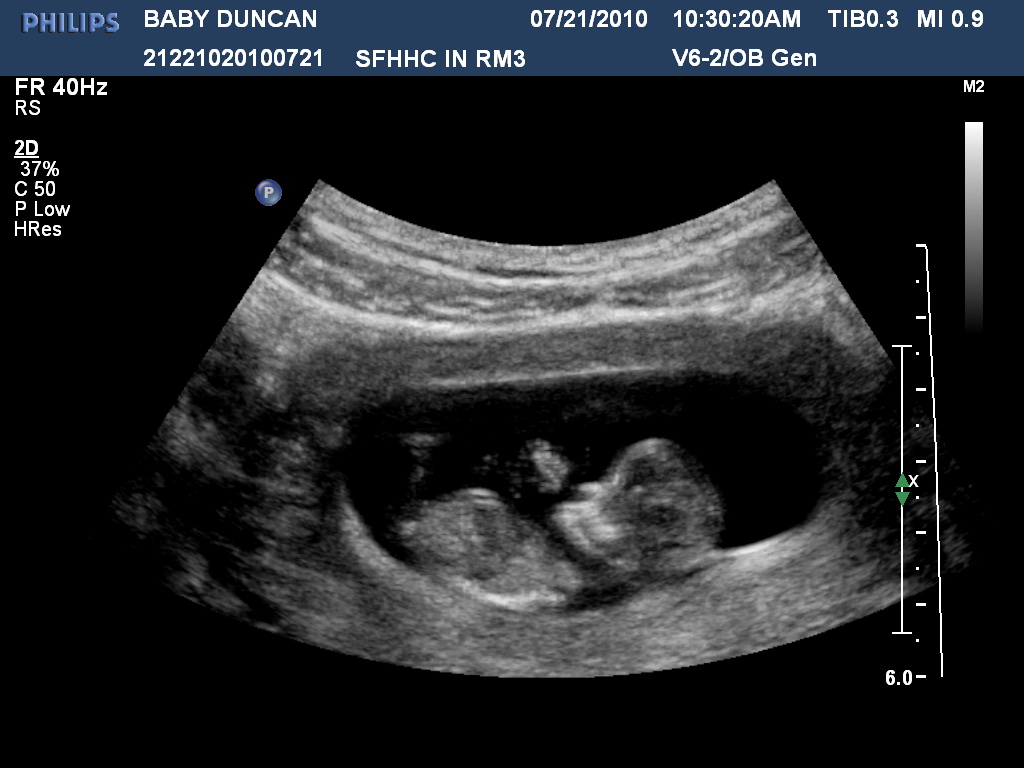

Today one of my really good friends at work, Megan, scanned me and got some good images of baby rooney and took some 3d shots. The baby must like Megan's voice because this is the ONLY ultrasound so far that he/she has sat still! This one baby rooney was waving hello.

I love this one you can see the baby's head and lil butt and stretched out leg!

This picture you can see a little nose/face, it's hard to see but definitely forming!

Head shot and you can see little arms also.